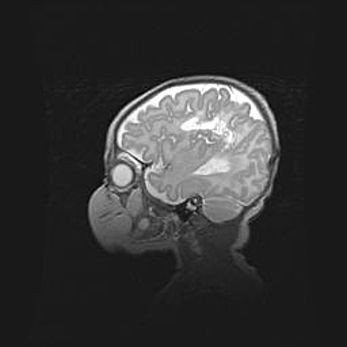

Аномалия Денди-Уокера. Признаки гипоплазии мозолистого тела.

Возраст: 5 месяцев 3 дня

Вес: 5550 г

Пол: мужской

Окружность головы: 39 см

Срок гестации: 40 недель

Аномалия Денди-Уокера – это порок развития головного мозга, для которого характерна триада симптомов: гипотрофия или аплазия червя мозжечка и/или полушарий мозжечка, расширение четвёртого желудочка с формированием ликворной кисты задней черепной ямки, гипертензионная гидроцефалия различной степени.

Гипоплазия мозолистого тела относится к дефектам внутриутробного этапа развития мозговой ткани, возникающим в процессе закладки структур головного мозга, что происходит на начальных этапах развития эмбриона.